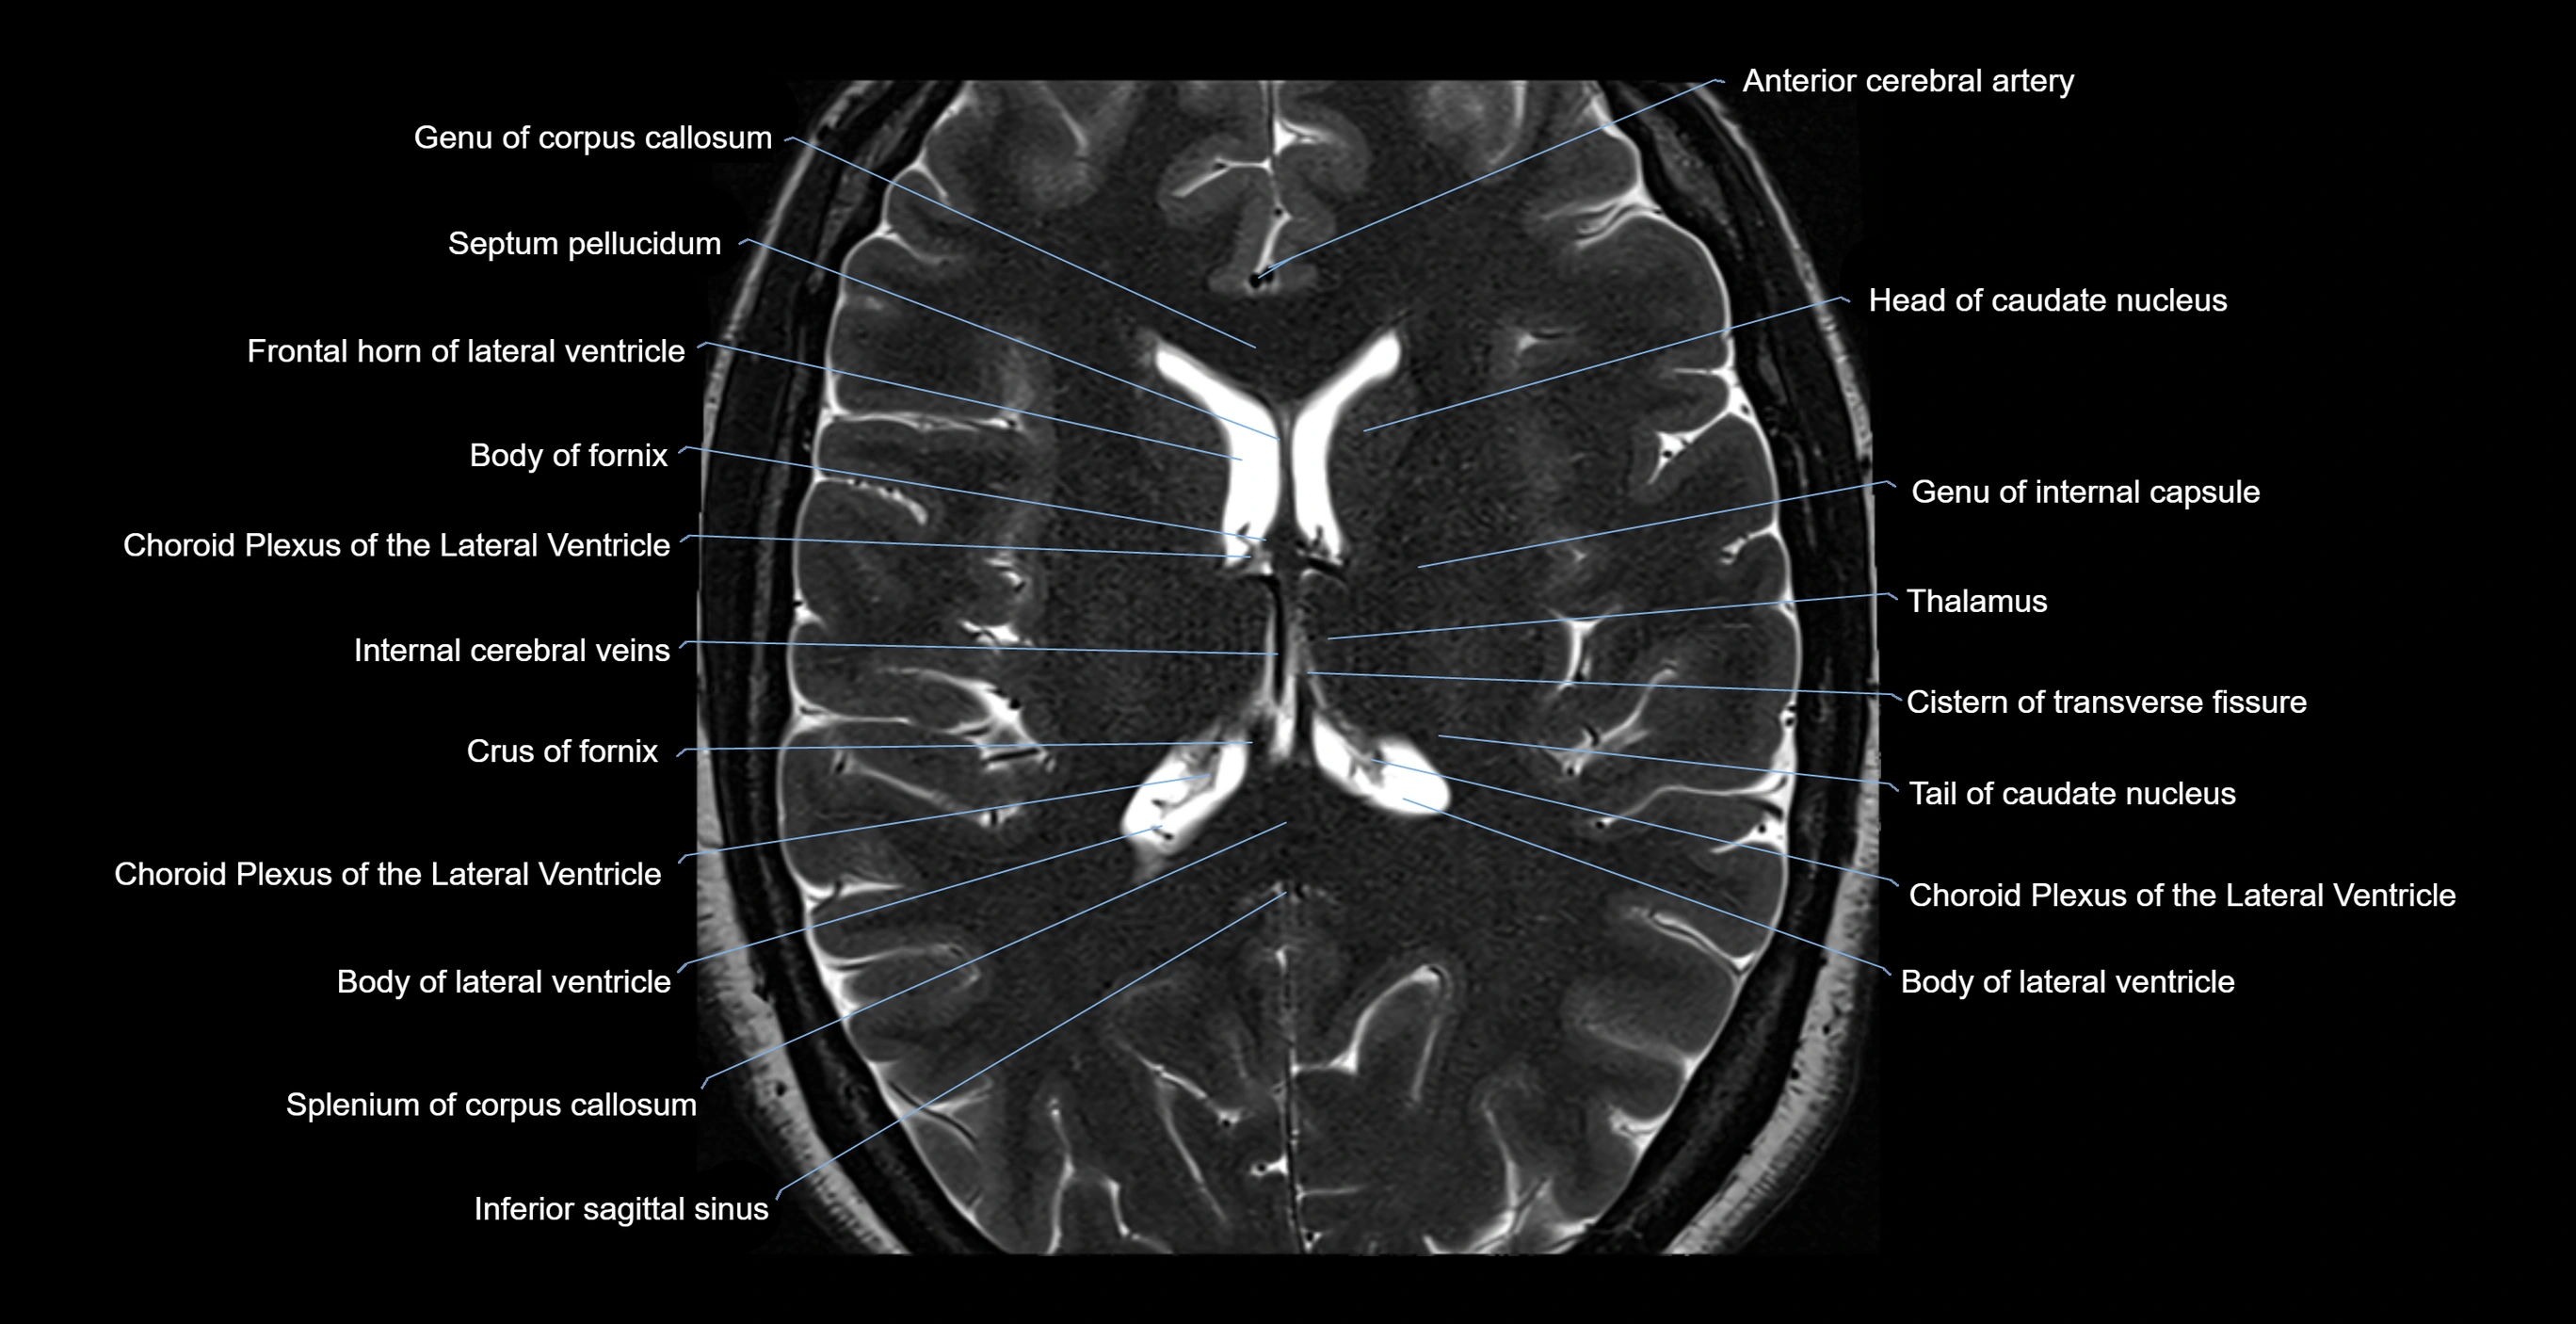

- Anterior cerebral artery

- Body of caudate nucleus

- Body of corpus callosum

- Body of fornix

- Body of lateral ventricle

- Choroid plexus of the lateral ventricle

- Cistern of transverse fissure

- Column of fornix

- Crus of fornix

- Frontal horn of lateral ventricle

- Genu of corpus callosum

- Head of caudate nucleus

- Inferior sagittal sinus

- Internal cerebral vein

- Splenium of corpus callosum

- Tail of caudate nucleus

- Thalamus

- genu of internal capsule